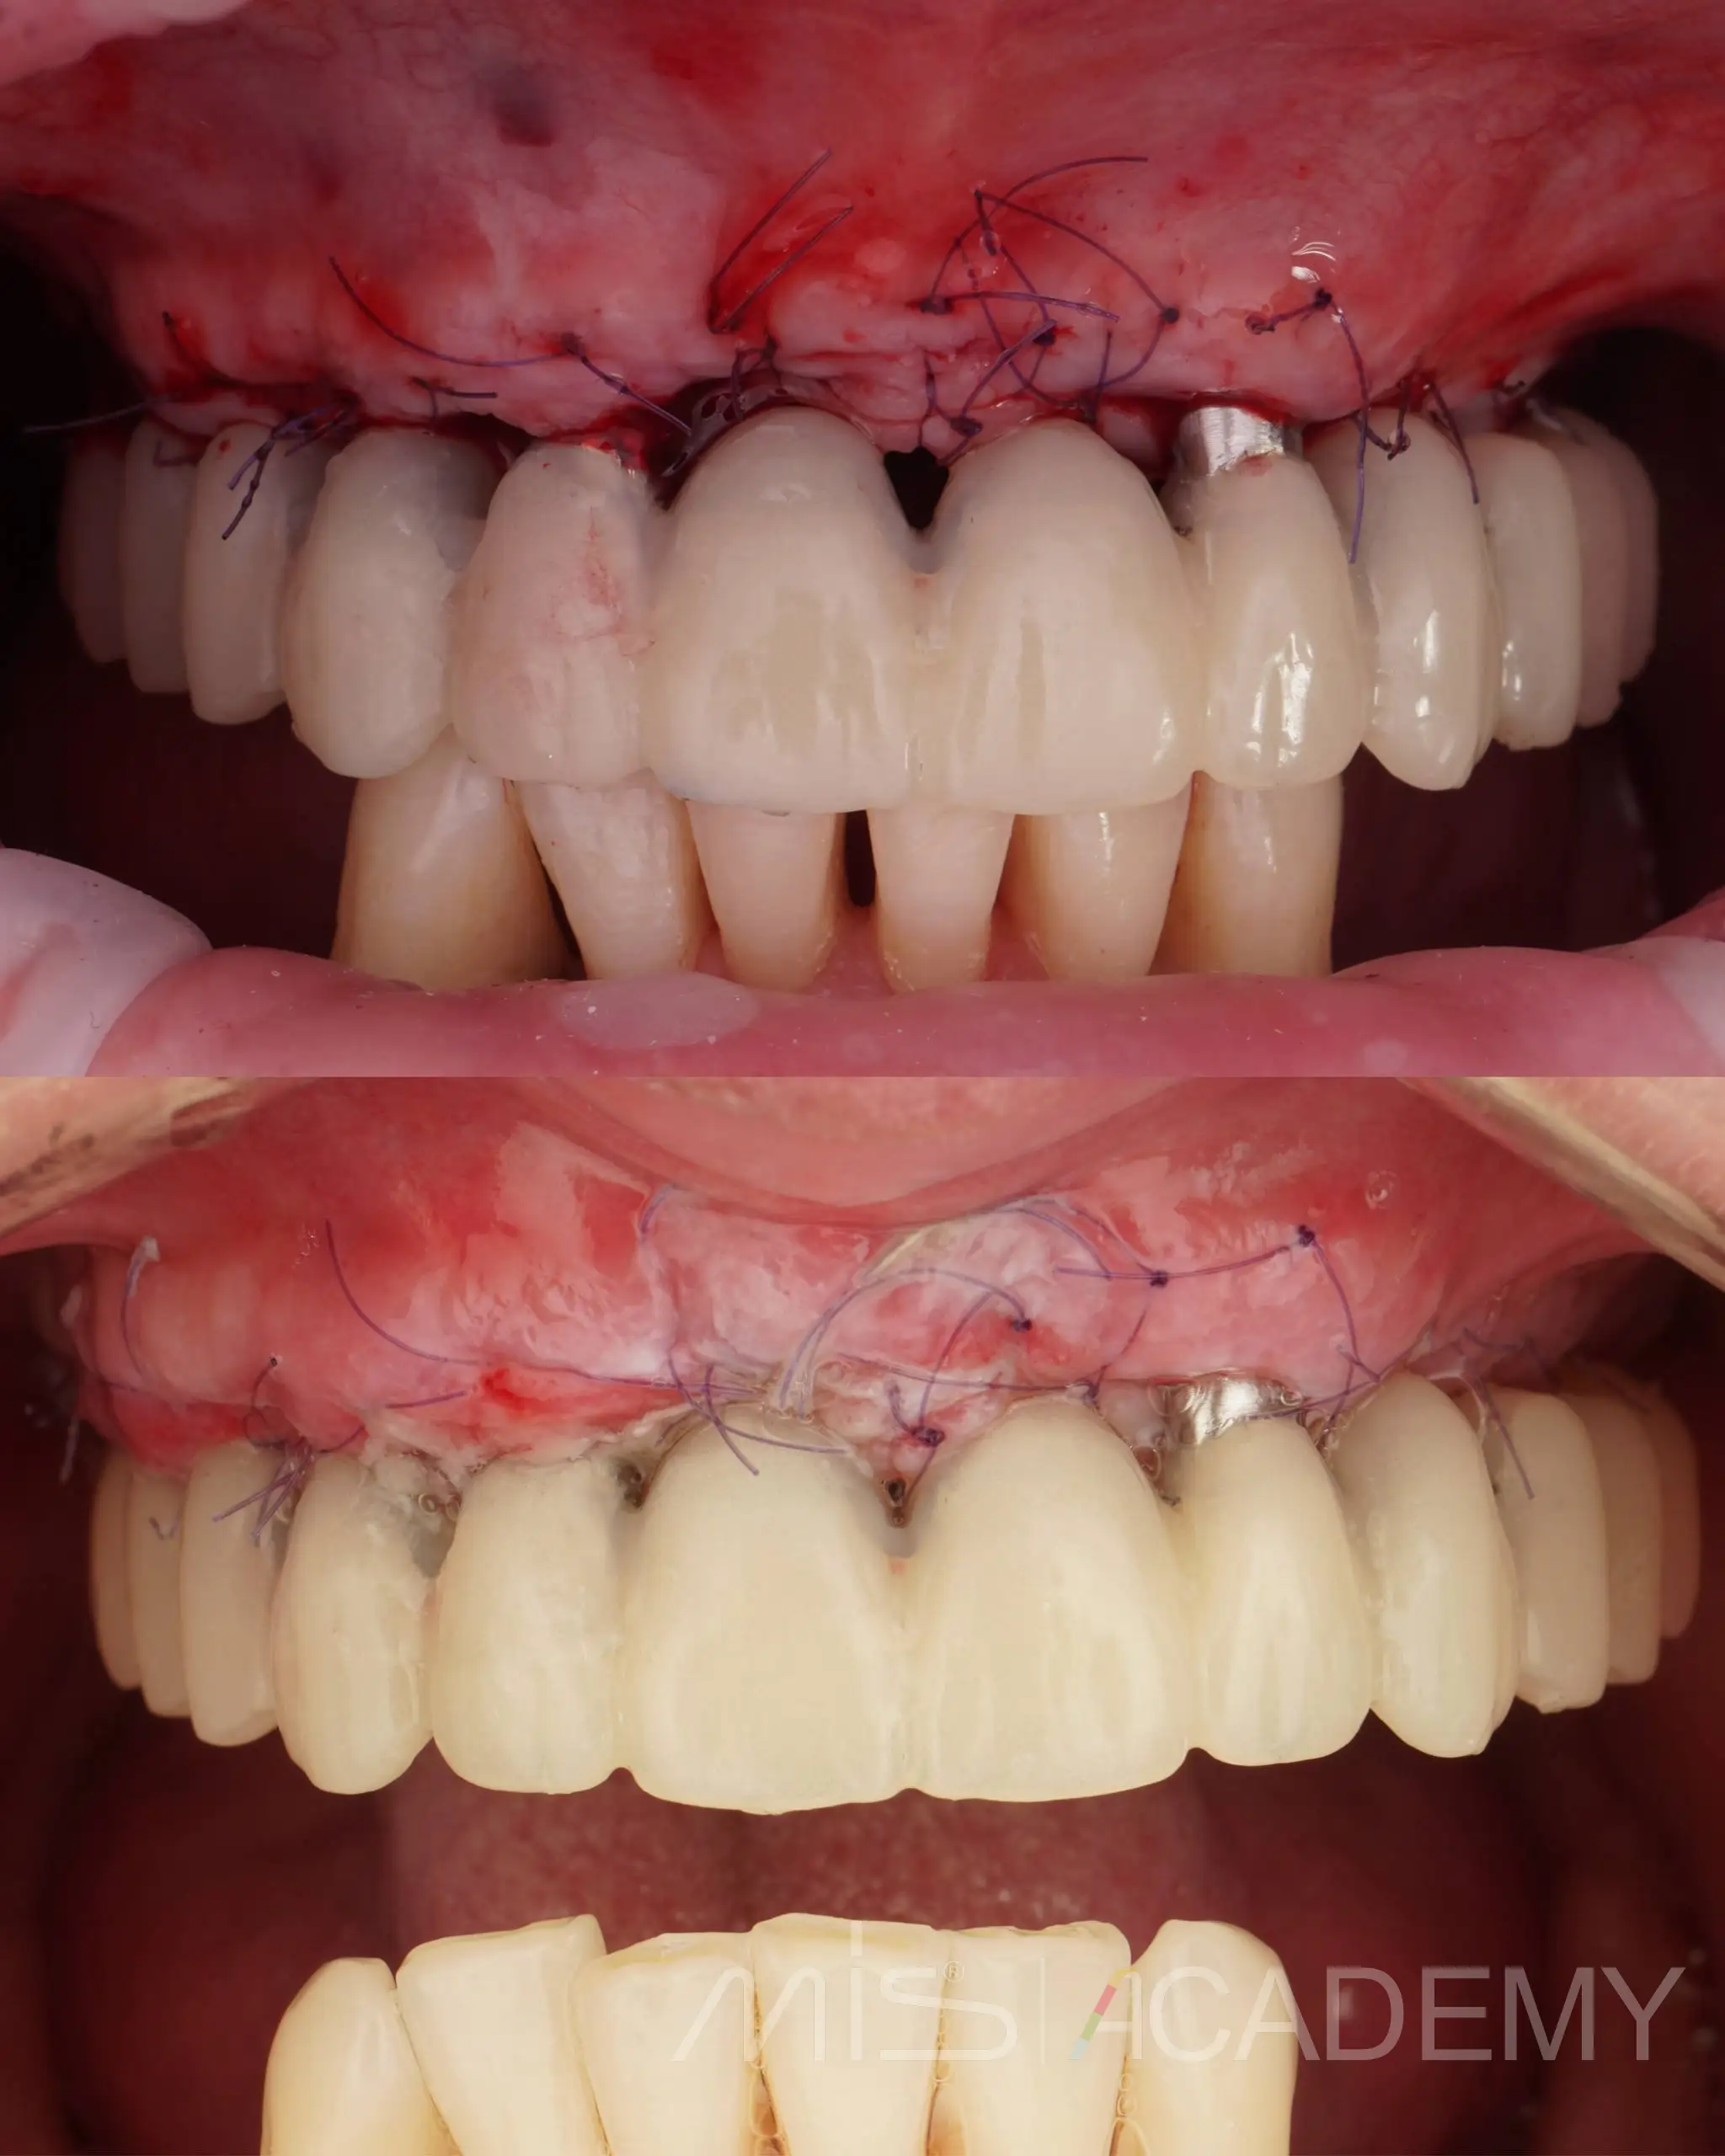

— Четыре имплантата в переднем отделе нагружены временной армированной конструкцией, разборная балка сварена непосредственно в полости рта, с уровня коннектов и угловых мультиюнитов.

— Во всех зонах имплантатов и понтиков выполнена пластика мягких тканей.